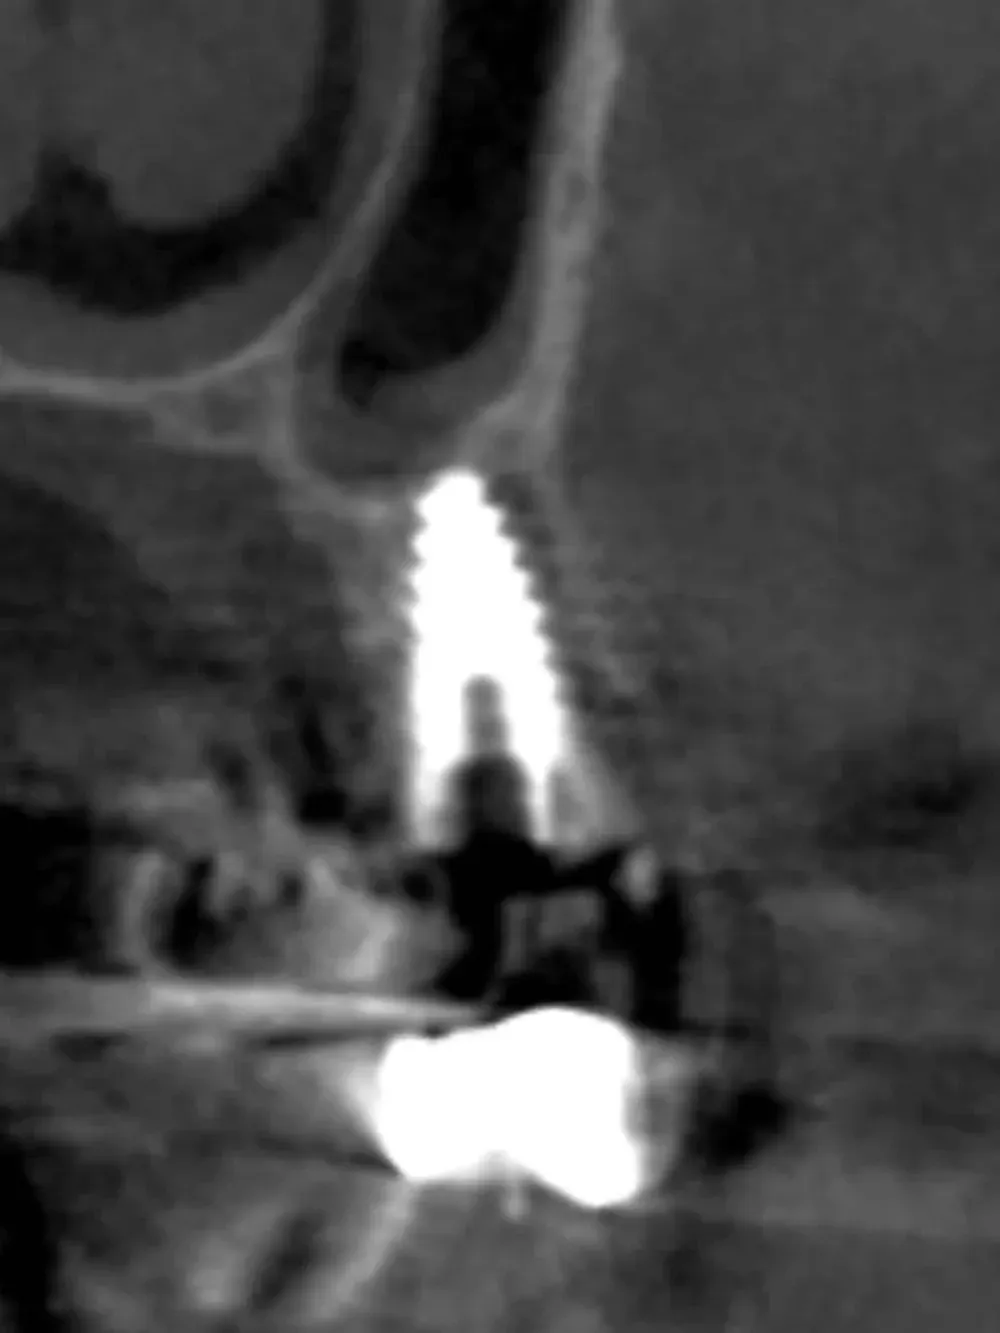

La CBCT intraoperatoria ha confermato la corretta posizione tridimensionale degli espansori e il raggiungimento della corticale del pavimento del seno in zona 2.5. In caso di dubbi sulla posizione e nel corso di interventi delicati come questo, questo ausilio strumentale è di fondamentale importanza. Ma non è sempre necessaria. L’esposizione, per quanto contenuta, dev’essere sempre ridotta al minimo, compatibilmente con la sicurezza chirurgica.

Sezione espansore sito 2.5

CBCT Post-op: Impianto in posizione 2.5 infracrestale con sollevamento della corticale del pavimento del seno